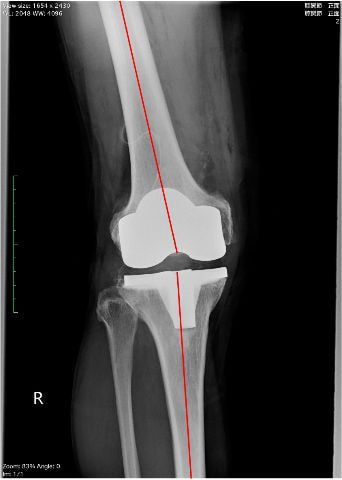

術後3日目から松葉杖歩行を開始しました。人工膝関節置換術後はO脚が改善し(右写真)、右脚に体重をかけて歩くことも早期に可能になります。術後5日目には、松葉杖を使用せずに両脚で歩くことが可能になりました。入院中は下肢筋力強化練習や歩行練習を反復することにより、日に日に歩行が安定して行えるようになります。